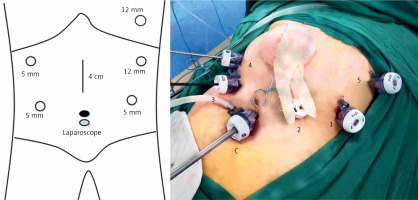

The patient was placed in the lithotomy position, with the head raised to approximately 45° to 60°. The surgeon was on the left side of the patient, the first assistant was on the right side of the patient, and the laparoscopic camera operator was between the patient’s legs. The six-port method (Figure 1) was used: the camera port was located below the umbilicus, Port 1 (12 mm) was located 2 cm below the costal margin on the left anterior axillary line, Port 2 (5 mm) was located 2 cm above the umbilicus on the left midclavicular line, Port 3 (5 mm) was located 2 cm above the umbilicus on the right midclavicular line, and Port 4 (5 mm) was located 2 cm below the costal margin on the right anterior axillary line. Port 5 (12 mm) was located in the sixth and seventh intercostal space on the right anterior axillary line (Figure 1).